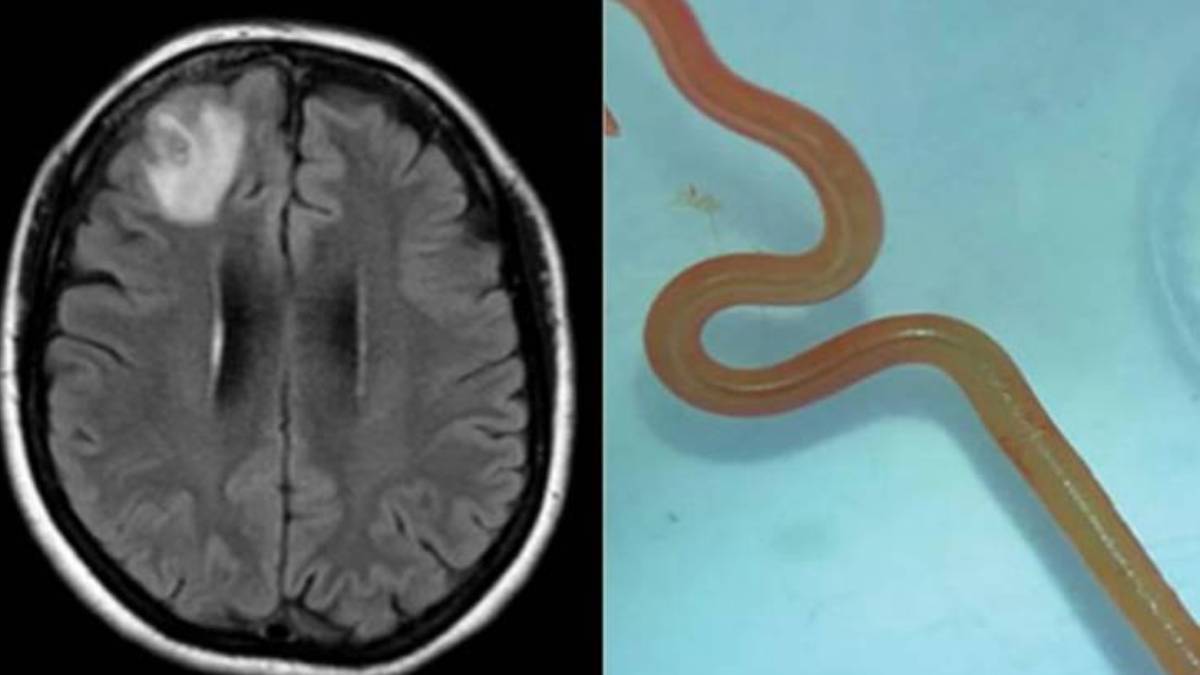

Kadının hastalığı çözülemezken bir anda unutkanlık etkisini gösterdi. Kadın ardından deprasyona girerek kendini iyice dış dünyaya kapattı. Bunun üzerine doktorlar MRI talep etti. Sonuçta kadının beyninin sağ ön lobunda hayaletimsi bir parıltı görüldü.

Beyin cerrahları duruma el attı ve kadının beyninden incelemek için bir doku aldı. Yapılan incelemelerde kadının beyninde şüpheli ip benzeri bir yapı fark edildi. Forsepsle çıkarılan şey pembemsi kırmızı renkte, bir kalemin yaklaşık yarısı uzunluğundaydı ve kıpırdıyordu. Böyle kadının hayatını cehenneme çeviren şeyin bir solucan olduğu anlaşıldı.

Solucanın ise ophidascaris robertsi olduğu anlaşıldı. Aslında yılanlarda görülen bu solucanın yol açtığı enfeksiyon ilk kez bir insanda görülüyordu.